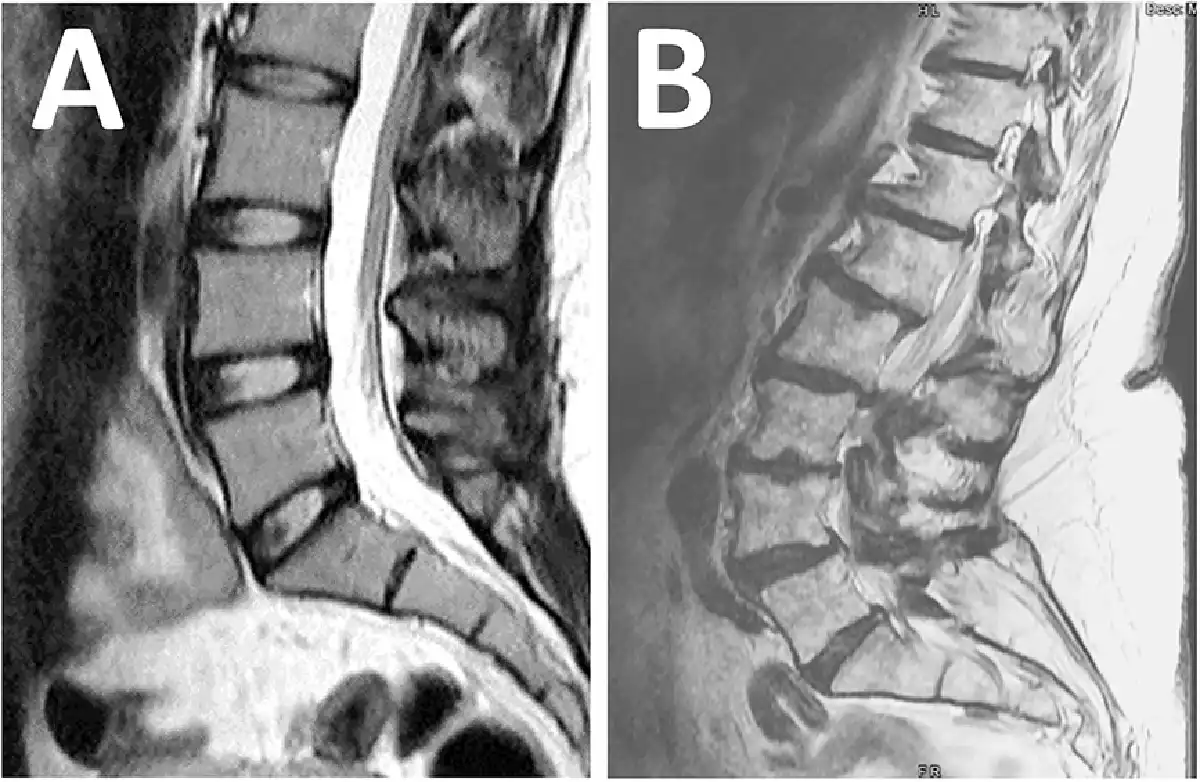

Magnetic resonance imaging: (A) normal findings with no pathology; (B) abnormal findings with multiple abnormalities not suitable for surgery.

A third aspect of step B was for the spine surgeon to assess the lumbosacral MRI for the presence of a surgically treatable lumbosacral annular tear., All lumbosacral MRI had to have been of appropriate technical quality and performed within 12 months of clinical evaluation. The use of contrast material during the MRI procedure was not required unless there was previous lumbosacral spine surgery at the site of the annular tear. The following lumbosacral MRI categorization system was utilized. The patient was not considered a surgical candidate if there were no lumbosacral annular tears (Figure 3A) or if the patient had multilevel abnormalities where risks of surgery outweighed benefits (Figure 3B). The patient was a surgical candidate if the lumbosacral MRI revealed annular tears at 1, 2, or 3 spinal levels that could be treated by LESS. We then further classified the annular tear by severity per the following criteria: subtle if a disc bulge or protrusion was visualized but there was no accompanying high-intensity zone (Figure 4, A and B) and obvious if a high-intensity zone was visualized on the axial and sagittal T2-weighted images (Figure 4, D and E).